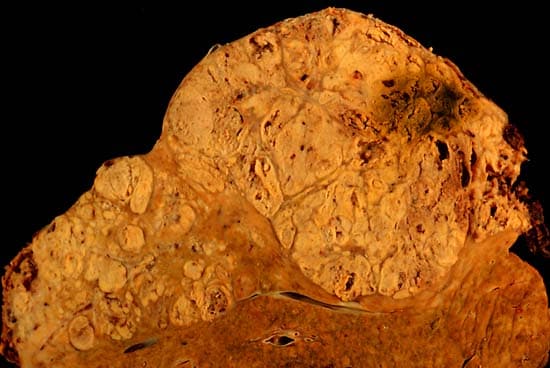

Hepatocellular carcinoma (HCC) is the most common type of primary liver cancer in adults and is currently the most common cause of death in people with cirrhosis. HCC is the third leading cause of cancer-related deaths worldwide. The development of HCC is attributed to fibrosis and cirrhosis, which occur in the setting of chronic liver injury and inflammation. The latter being closely linked to chronic viral hepatitis infection (hepatitis B or C) or exposure to toxins such as alcohol, aflatoxin, or pyrrolizidine alkaloids. Certain diseases, such as hemochromatosis and alpha 1-antitrypsin deficiency, markedly increase the risk of developing HCC. Metabolic syndrome and NASH are also increasingly recognized as risk factors for HCC. As with any cancer, the treatment and prognosis of HCC vary depending on the specifics of tumor histology, size, how far the cancer has spread, and overall health. The vast majority of HCC cases and the lowest survival rates after treatment occur in Asia and sub-Saharan Africa, in countries where hepatitis B infection is endemic and many are infected from birth. The incidence of HCC in the United States and other developing countries is increasing due to an increase in hepatitis C virus infections. It is more than four times as common in males as in females, for unknown reasons. Most cases of HCC occur in people who already have signs and symptoms of chronic liver disease. They may present with worsening symptoms or without symptoms at the time of cancer detection. HCC may present with non-specific symptoms such as abdominal pain, nausea, vomiting, or feeling tired. Some symptoms that are more closely associated with liver disease include yellow skin (also called jaundice), abdominal swelling due to fluid in the abdominal cavity, easy bruising from blood clotting abnormalities, loss of appetite, unintentional weight loss, abdominal pain, nausea, vomiting, or feeling tired. Since HCC mostly occurs in people with cirrhosis of the liver, risk factors generally include factors which cause chronic liver disease that may lead to cirrhosis.